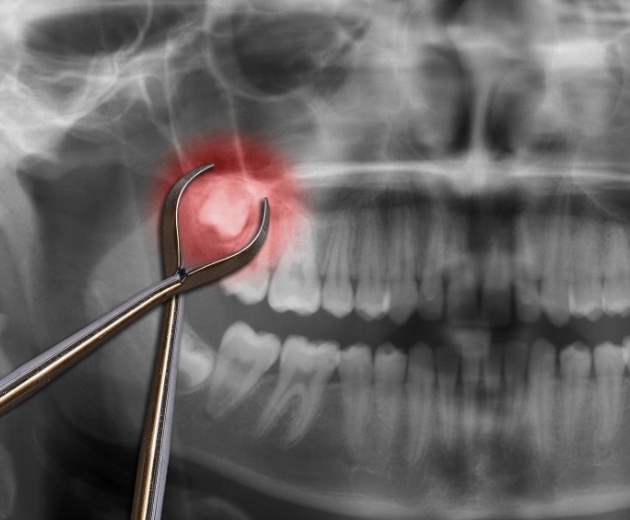

Impacted

Wisdom Teeth

The wisdom teeth typically erupt during the late teens or early 20s, which is long after all the other teeth have erupted. Without enough space to emerge, the wisdom teeth often become trapped underneath the gums, which is not only painful, but tends to increase the risk of infection. Impacted wisdom teeth can be removed as soon as it’s determined that they are likely to cause problems in the mouth.

The team at Northern Virginia Oral, Maxillofacial & Implant Surgery first examines your smile to determine whether your wisdom teeth are posing enough of a threat to your health to necessitate extraction. They visually examine your smile and take panoramic or digital X-rays to aid in their evaluation.